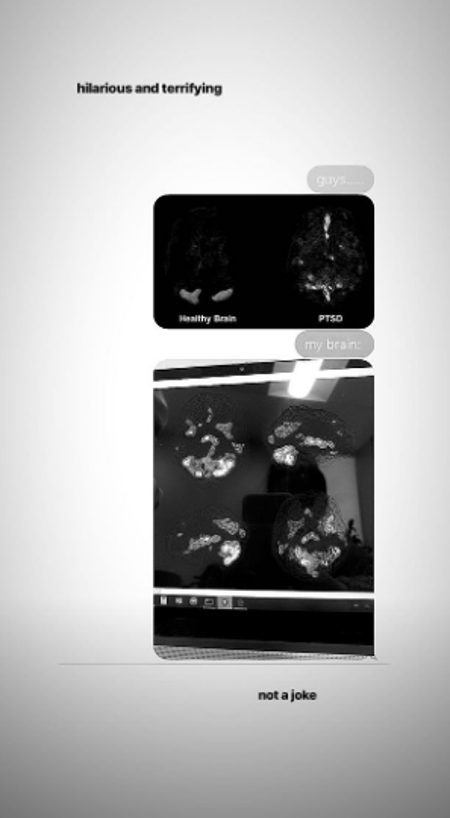

Ariana Grande je fanovima pružila uvid u svoju borbu s PTSP-om (post-traumatski stresni poremećaj) koji je posljedica  bombaškog napada u Manchesteru 2017. godine. Slika prikazuje dva bočna skeniranja "zdravog mozga" i mozga s PTSP-om. Ariana je objavila fotografije koje prikazuju kako zdrav mozak izgleda i kako izgleda mozak s PTSP-om. Nakon skeniranja, ispostavilo se kako Ariana boluje od te bolesti.

Uz objavu je napisala: "Smiješno i strašno, nije šala".